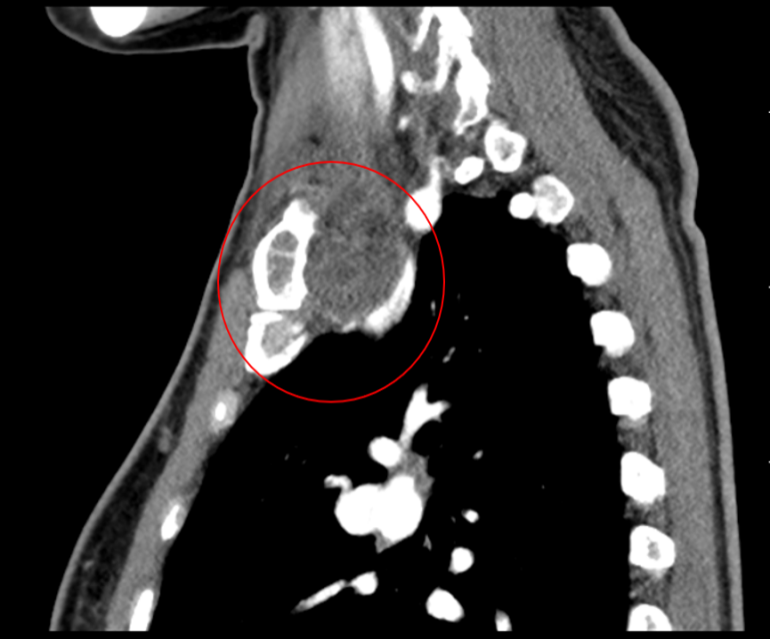

患者50岁女性,因体检发现右锁骨肿物10余天来诊。入院后X光片示右锁骨胸骨端膨大,密度减低,CT及MRI检查提示右侧锁骨局部骨性凸起伴周围肿块形成,考虑右锁骨胸骨端软骨肉瘤。

图片 1.png